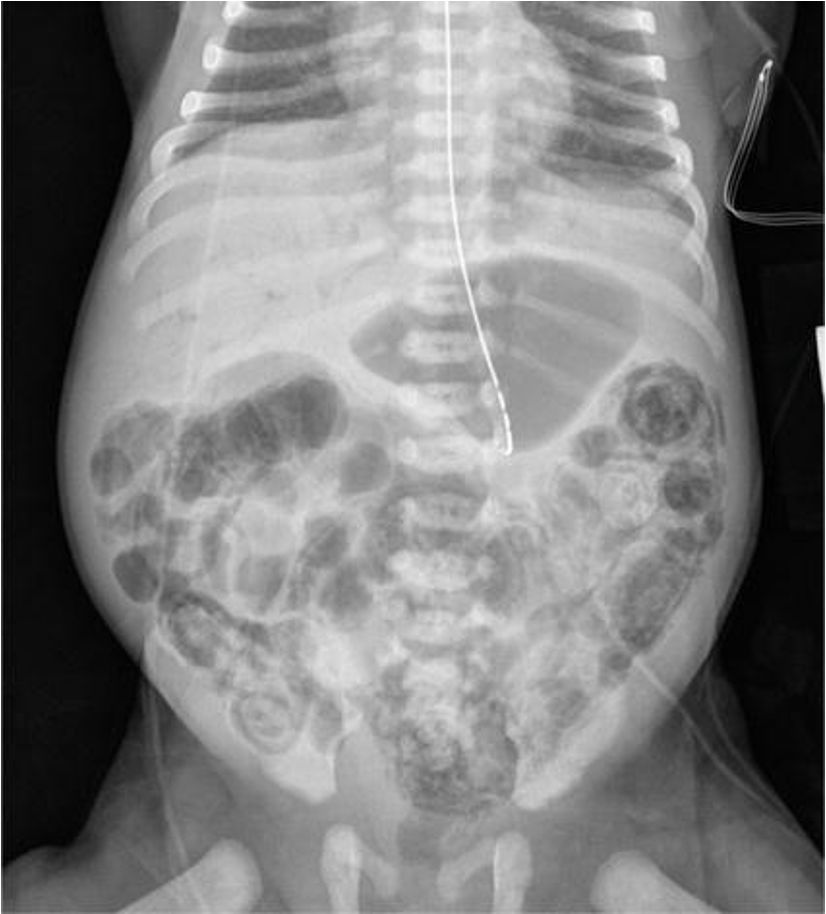

What is your spot diagnosis? necrotizing enterocolitis

- Dilated loops,

- thickened bowel walls,

- pneumatosis intestinalis (air in intestinal walls),

- pneumoperitoneum; indicate perforation (emergency requiring surgical intervention),

- portal gas (present in the portal venous system,

- considered to be a poor prognostic sign).

inflamed, necrosis ⇒ Perforation everywhere

dark circles air in intestinal wall

Air in portal gas